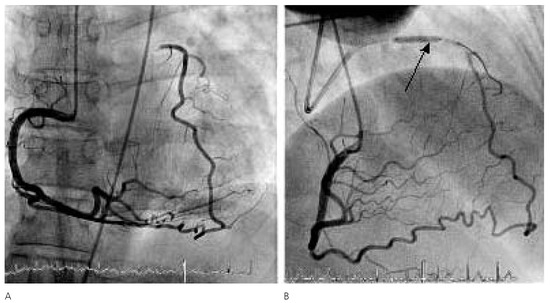

Six Simultaneously Employed Methods to Gauge the Coronary Collateral Flow of the Decade

by Steffen Gloekler, Tobias Rutz and Christian Seiler

Case report. A 59-year-old woman with bronchial asthma and obesity underwent coronary angiography because of exertional dyspnea and atypical chest pain both at rest and sometimes during exertion[...] Full article